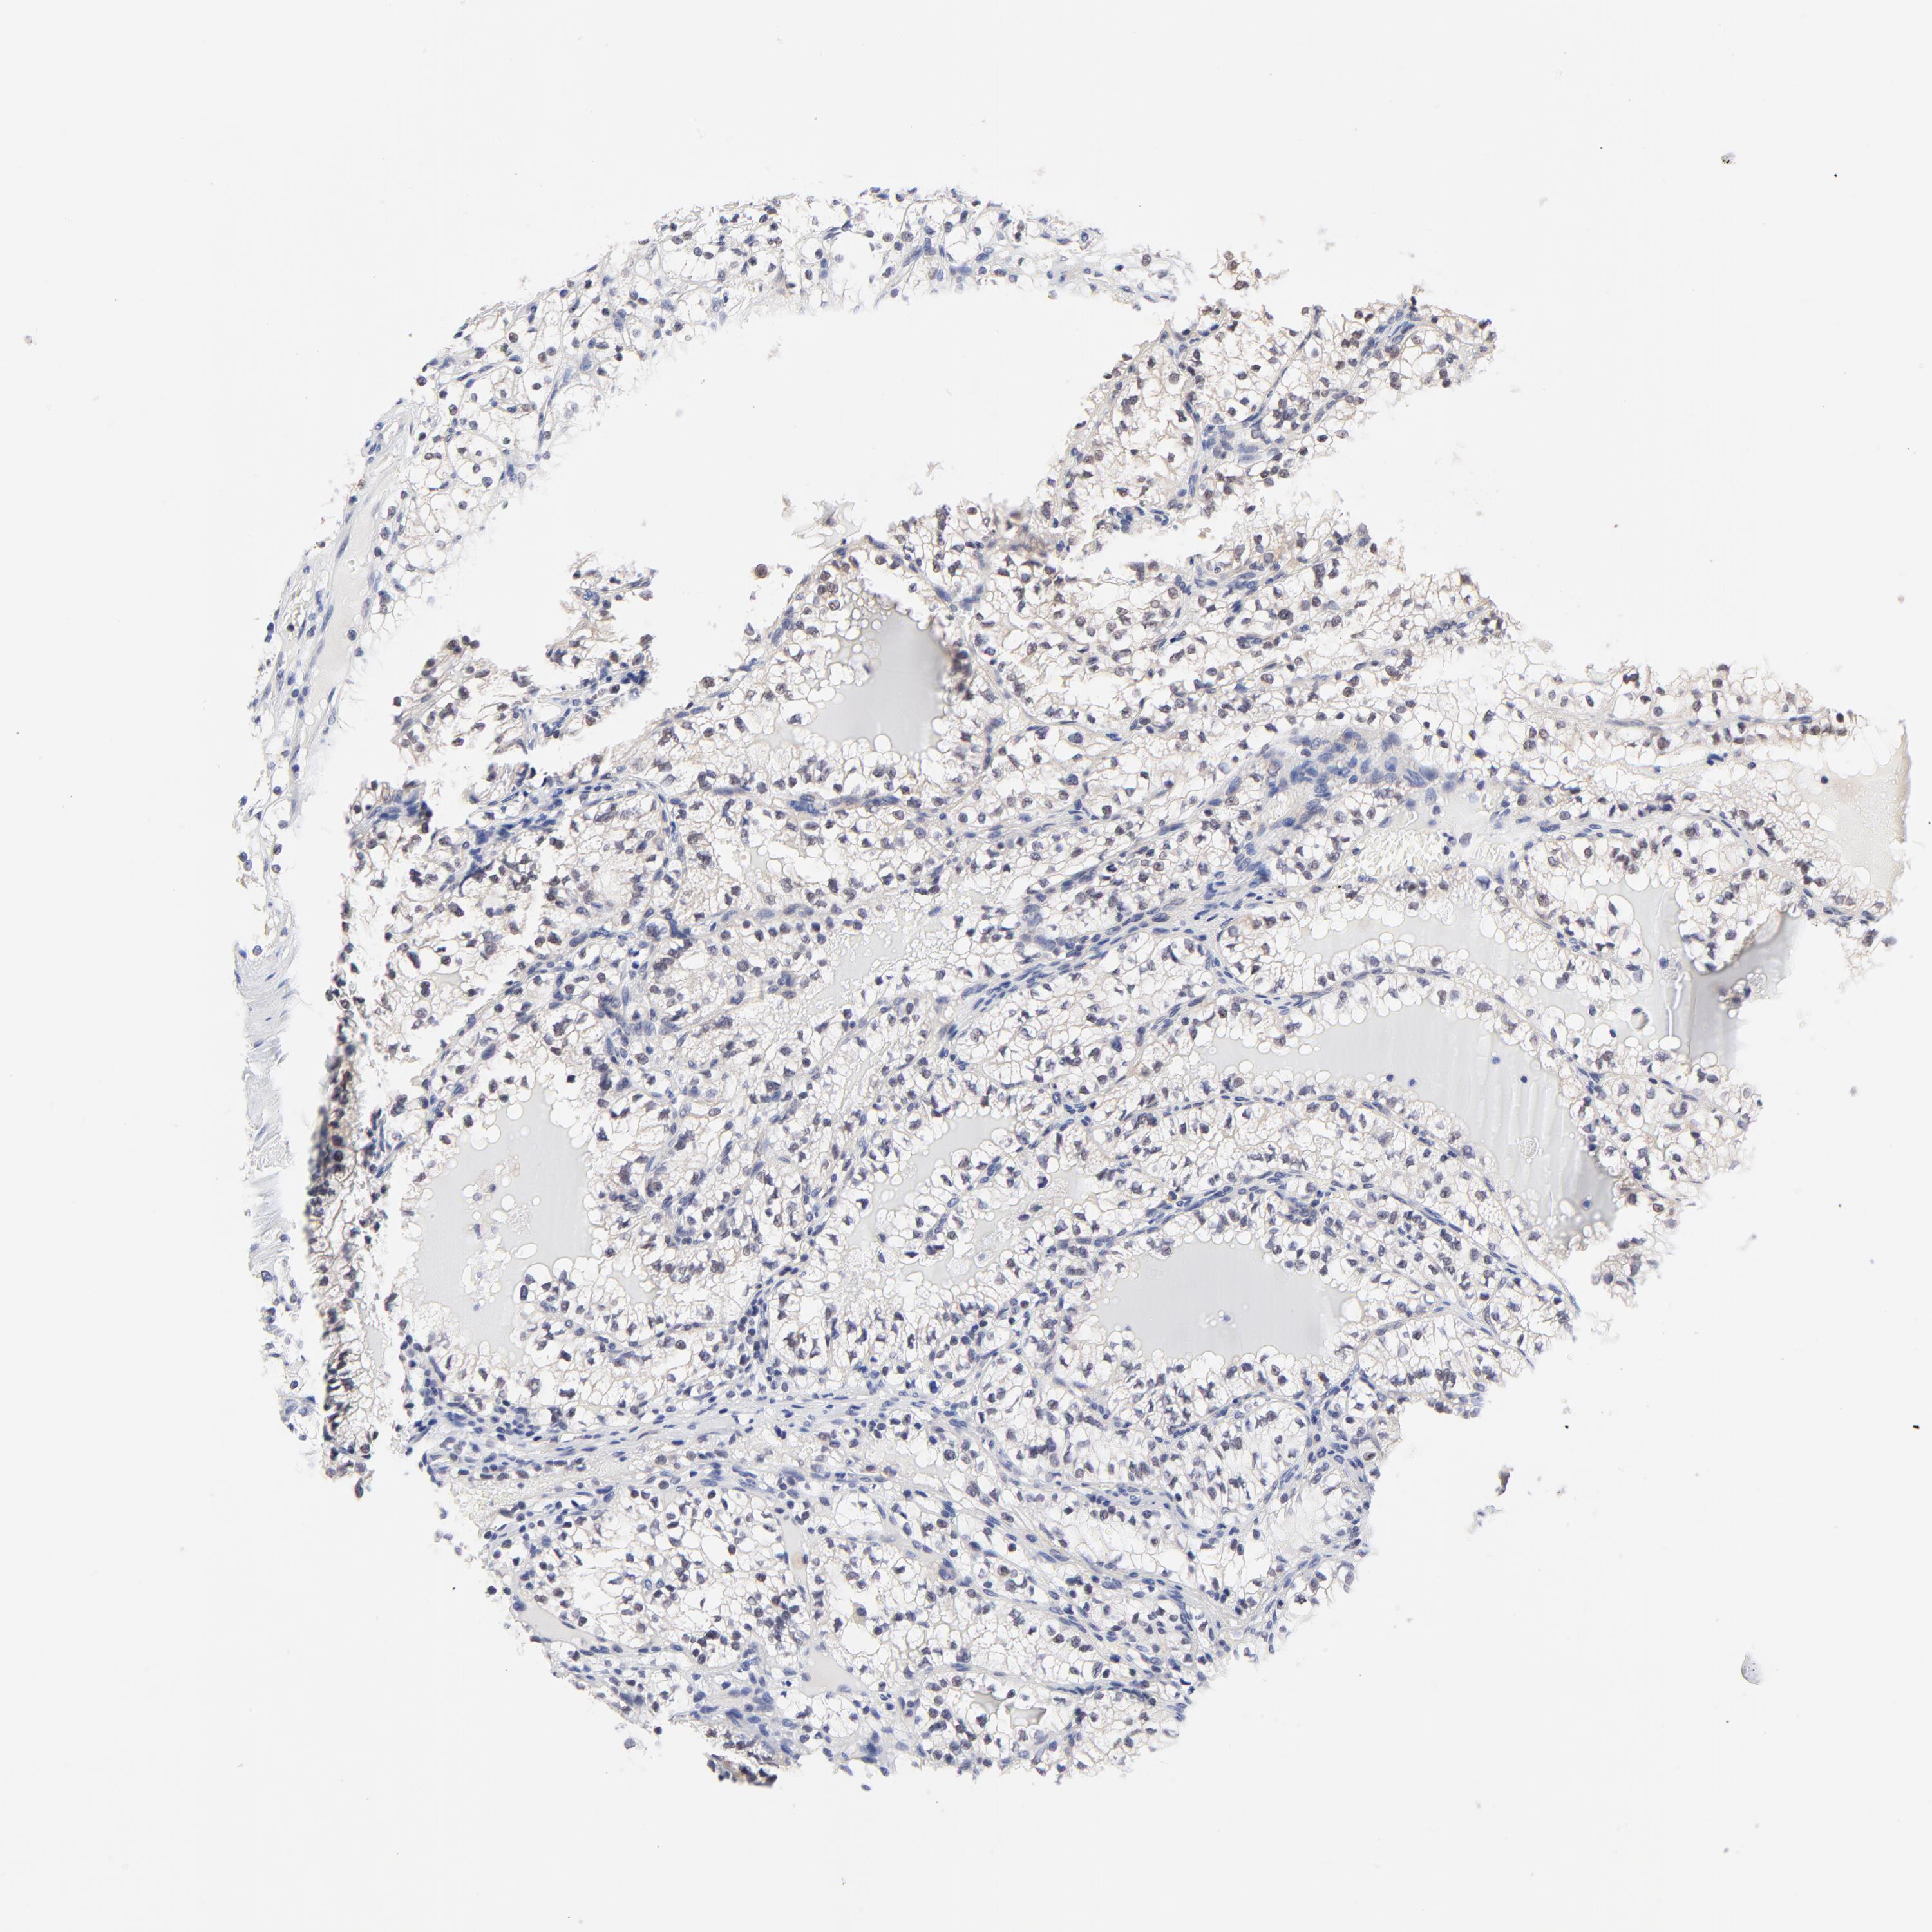

KIDNEY RENAL CLEAR CELL CARCINOMA (VALIDATION) - Interactive survival scatter ploti

The Survival Scatter plot shows the clinical status (i.e. dead or alive) for all individuals in the patient cohort, based on the same data that underlies the corresponding Kaplan-Meier plots. Patients that are alive at last time for follow-up are shown in blue and patients who have died during the study are shown in red.

The x-axis shows the expression levels (FPKM) of the investigated gene in the tumor tissue at the time of diagnosis. The y-axis shows the follow-up time after diagnosis (years). Both axes are complimented with kernel density curves demonstrating the data density over the axes. The top density plot shows the expression levels (FPKM) distribution among dead (red) and alive patients (blue). The right density plot shows the data density of the survived years of dead patients with high and low expression levels respectively, stratified using the cutoff indicated by the vertical dashed line through the Survival Scatter plot. This cutoff is automatically defined based on the FPKM cutoff that minimizes the p-score. The cutoff can be changed by dragging the vertical line or by entering a cutoff value in the square labeled "Current cut-off".

Under the Survival Scatter plot the p-score landscape (black curve; left axis) is shown together with dead median separation (red curve; right axis). Dead median separation is the difference in median mRNA expression between patients who have died with high and low expression, respectively. It is calculated as follows: median FPKM expression of dead patients with high expression - median FPKM expression of dead patients with low expression. This is intended to aid the user in visually exploring custom cutoffs and the associated p-scores and dead median separation.

Individual patient data is displayed and can be filtered by clicking on one or more of the category buttons on the top of the page. Categories describing expression level and patient information include: high, low, alive, dead, female, male and tumor stages. The scale of the x-axis can be toggled between linear and log-scale by clicking on the "x log" button. Mouse-over function shows TCGA ID, patient information and mRNA expression (FPKM) for each patient.

& Survival analysisi

Kaplan-Meier plots summarize results from analysis of correlation between mRNA expression level and patient survival. Patients were divided based on level of expression into one of the two groups "low" (under cut off) or "high" (over cut off). X-axis shows time for survival (years) and y-axis shows the probability of survival, where 1.0 corresponds to 100 percent.

FBXO8 is validated prognostic, high expression is favorable in Kidney Renal Clear Cell Carcinoma (validation)

: 21.74

Average pTPM 20.8

Number of samples 100